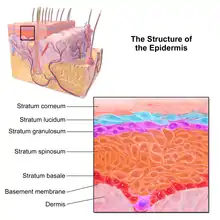

Microscopic image showing the layers of the epidermis. The stratum corneum appears more compact in this image than above because of different sample preparation. | |

The epidermis is composed of 4 or 5 layers, depending on the region of skin being considered.[10] Those layers from outermost to innermost are:[2]

- cornified layer (stratum corneum)

- Composed of 10 to 30 layers of polyhedral, anucleated corneocytes (final step of keratinocyte differentiation), with the palms and soles having the most layers. Corneocytes contain a protein envelope (cornified envelope proteins) underneath the plasma membrane, are filled with water-retaining keratin proteins, attached together through corneodesmosomes and surrounded in the extracellular space by stacked layers of lipids.[11] Most of the barrier functions of the epidermis localize to this layer.[12]

Confocal image of the stratum corneum - clear/translucent layer (stratum lucidum, only in palms and soles)

- This narrow layer is found only on the palms and soles. The epidermis of these two areas is known as "thick skin" because with this extra layer, the skin has 5 epidermal layers instead of 4.

- granular layer (stratum granulosum)

- Keratinocytes lose their nuclei and their cytoplasm appears granular. Lipids, contained into those keratinocytes within lamellar bodies, are released into the extracellular space through exocytosis to form a lipid barrier that prevents water loss from the body as well as entry of foreign substances. Those polar lipids are then converted into non-polar lipids and arranged parallel to the cell surface. For example glycosphingolipids become ceramides and phospholipids become free fatty acids.[11]

Confocal image of the stratum granulosum - spinous layer (stratum spinosum)

- Keratinocytes become connected through desmosomes and produce lamellar bodies, from within the Golgi, enriched in polar lipids, glycosphingolipids, free sterols, phospholipids and catabolic enzymes.[3] Langerhans cells, immunologically active cells, are located in the middle of this layer.[11]

Confocal image of the stratum spinosum already showing some clusters of basal cells - basal/germinal layer (stratum basale/germinativum)

- Composed mainly of proliferating and non-proliferating keratinocytes, attached to the basement membrane by hemidesmosomes. Melanocytes are present, connected to numerous keratinocytes in this and other strata through dendrites. Merkel cells are also found in the stratum basale with large numbers in touch-sensitive sites such as the fingertips and lips. They are closely associated with cutaneous nerves and seem to be involved in light touch sensation.[11]

Confocal image of the stratum basale already showing some papillae - Malpighian layer (stratum malpighii)

- This is usually defined as both the stratum basale and stratum spinosum.[4]

The epidermis is separated from the dermis, its underlying tissue, by a basement membrane.

Cross-section of all skin layers Illustration of epidermal layers

Illustration of epidermal layers Optical coherence tomography of fingertip